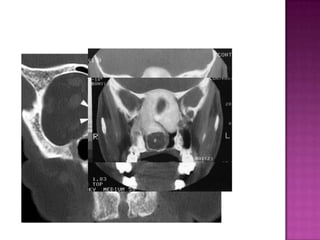

 „ CT and MRI are the common modalities

 „ CT is the most widely performed study

 „ bony changes

 „ bowing of the bones near the soft tissue

 mass

 Plain sinus radiographs are adequate for detecting

osteomas of paranasal sinuses.